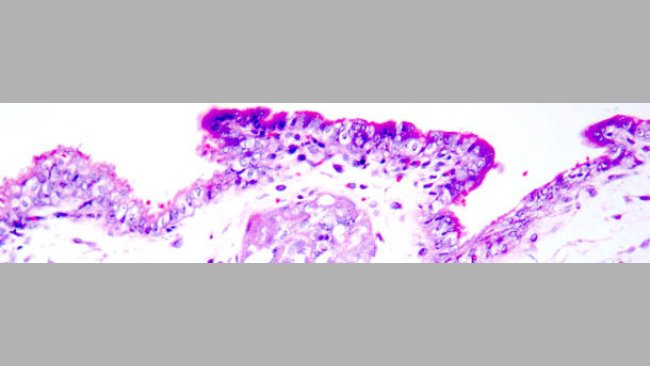

Eine PCV2-Impfung der Jungsauen vor der Besamung mit PCV2-infiziertem Sperma führt zu einem deutlich geringeren Virusgehalt sowie einer deutlich geringeren Virusausscheidung und somit zu einem besseren Schutz der Feten.

PCV2 kann bei infizierten Ebern über das Sperma ausgeschieden und damit durch eine KB auf Sauen übertragen werden. Dies stellt wiederum eine potenzielle Gefahr für Reproduktionsstörungen dar. Es gibt aber keine Anzeichen dafür, dass PCV2 Auswirkungen auf die Spermaqualität hat.